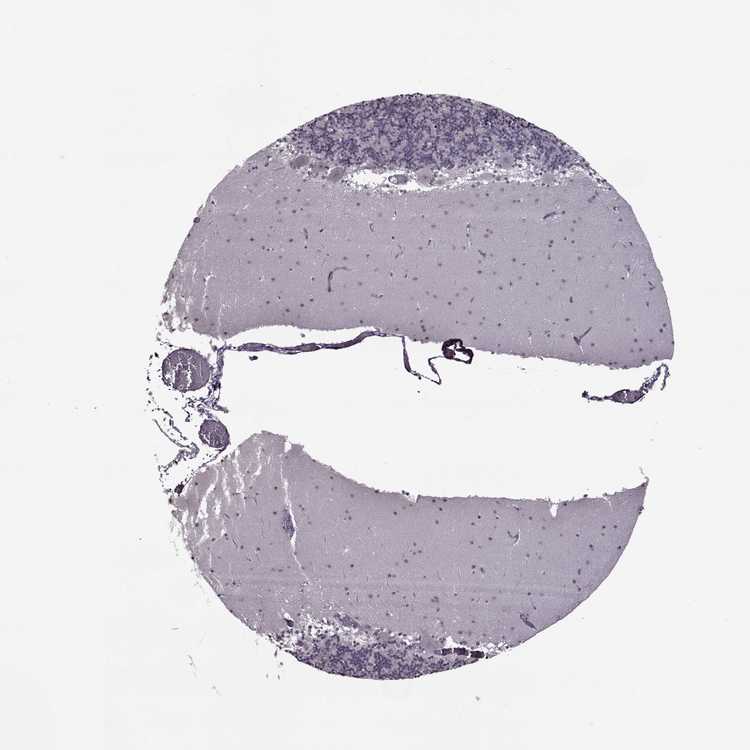

BRAIN CEREBELLUM Show tissue menu

CEREBELLUM - Expression summary

CEREBELLUM - Antibody stainingi

Antibody staining in the annotated cell types in the current human tissue is reported as not detected, low, medium, or high, based on conventional immunohistochemistry profiling in selected tissues. This score is based on the combination of the staining intensity and fraction of stained cells.

Each image is clickable and will lead to virtual microscopy that enables deeper exploration of all samples and also displays staining intensity scores, fraction scores and subcellular localization as well as patient and tissue information for each sample.

Antibody HPA046068Antibody HPA055623

Purkinje cells Not detectedNot detected

Cells in granular layer Not detectedNot detected

Cells in molecular layer Not detectedNot detected